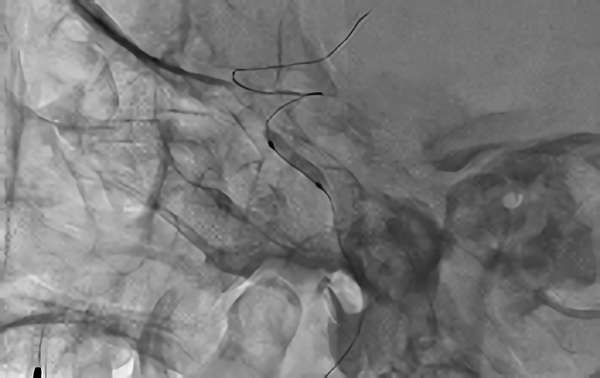

症例 '18年3月

No.

90

'18年3月28日

左内頚動脈狭窄症

70代

大阪府の病院

中

治療